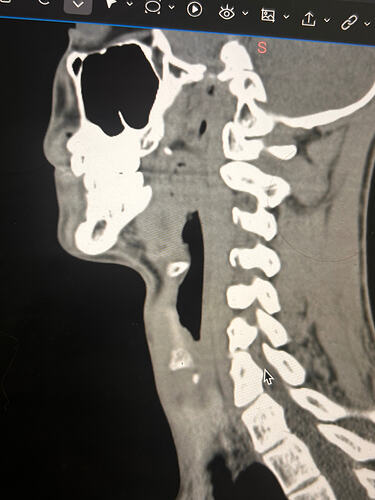

Here are some of my 2-d scans, thanks. The top one is my right greater horn and the bottom is the left

Thank you for the additional images. After reading @Jules observations, I went back over the first 4 images you sent & realized I’d miss some significant things. I’ve annotated more images for you below:

I totally missed that I could see your whole hyoid bone from the front in this image. Jules is right, your greater horns are very thick from top to bottom. You can also see that your left greater horn is pretty straight, but the right one has an upward curve to it. I’m not sure what the calcification is below your hyoid but it’s most likely thyroid since the thyroid sits just below the hyoid in the neck.

In this image, you can see the differences in the shapes of your hyoid’s greater horns. The right one is more curved but the left one is thicker in width medial to lateral. In this image from the front it looks like both greater horns may be contacting your cervical spine in certain head positions, but again, that may an illusion created by the angle of the image.

In the final two images you sent, the right greater horn is very close to your cervical spine so there’s a good chance it’s causing you some problems as well as possible carotid artery irritation or compression in different head positions. The image of the left one doesn’t show as much of the greater horn so I can’t tell how close to the spine it is. Can you back the left image out a bit so it looks more like the right one?